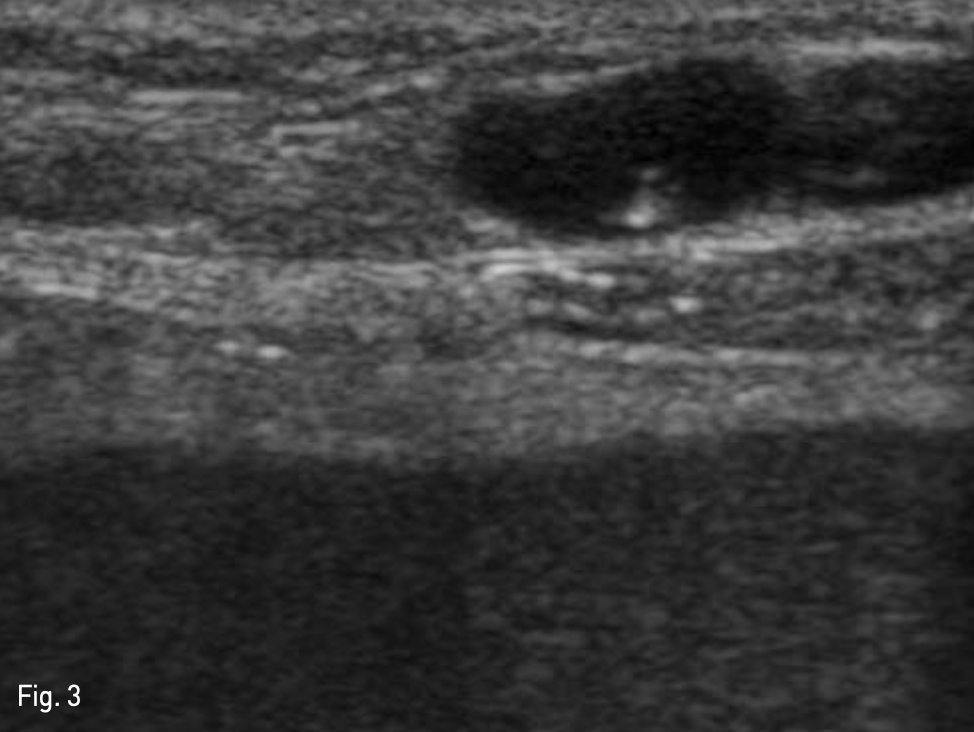

Fig. 3

Puncture of recanalized paraumbilical vein. US guided recanalized paraumbilical vein puncture was done for catheter insertion for portography which is assisted TIPS by visualization of anatomy of portal vein.

복벽에 확장되어 있는 recanalized paraumbilical vein을 초음파 유도하에 천자하여(Fig. 3), 왼쪽 문맥 으로 5-Fr 카테터를 삽입하였다. 문맥조영술을 시행하여 간내문맥을 확인하였다. Right intrnal jugular vein을 천자하여 5-Fr 카테터를 삽입하여 오른쪽 간정맥 조영술을 시행하고 오른쪽 간정맥을 신택한다. 이후 recanalized paraumbilical vein을 통한 문맥조영술 을 roadmap으로 이용하여 16G Colapinto needle (Cook Inc, Bloominglon, IN, USA) 오른쪽 간문맥을 천자하였다(Fig. 4). 천자된 경로를 6mm x 4cm balloon (Mustang, Boston Scientific, Massachusetts, USA)을 이용하여 확장하고, 10mm x 5cm partially covered stent (Niti-s TIPS Stent, Tae Woong medical, Gyeonggi-do, Korea)를 간문맥과 중간간정맥 샛길에 삽입하였다. 이후 스테트가 펴지지 않은 부분을 펴기위해 10mm x 4cm balloon (Mustang, Boston Scientific, Massachusetts, USA)을 이용해 확장하였다. TIPS stent를 설치한 후 시행한 문맥조영술에서 식도정맥류를 보이지 않았고 stent를 통한 원활한 혈류를 확인 할 수 있었다(Fig. 5). 문맥의 평균압력이 시술 전 22mmHg에서 시술 후 14mmHg로 감소하였고, 최대 정맥문맥 압력차이가 16mmHg에서 1mmHg로 감소하였다.